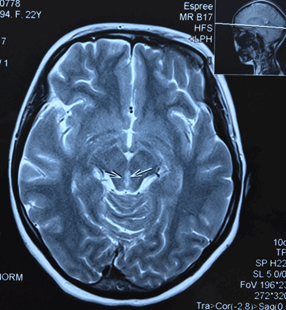

Пациентка направляется на МРТ головного мозга без контрастирования с подозрением на синдром Вернике и образование ГМ (рис.).

МРТ головного мозга без контрастирования пациентки Ч. Поражение вещества мозга по ходу паравентрикулярных отделов варолиева моста, водопровода и медиальных отделов таламуса

Результаты МРТ головного мозга пациентки: «Топография срединных структур мозга не изменена. Обращает внимание поражение вещества мозга по ходу паравентрикулярных отделов варолиева моста, водопровода и медиальных отделов таламуса. В белом веществе лобно-теменных долей с обеих сторон определяются очаги лейкопатии. Мозолистое тело, гипоталамо-гипофизарная область, продолговатый мозг и мозжечок без особенностей. Область мостомозжечковых углов без патологических изменений. Желудочковая система мозга не расширена и не деформирована. Конвекситальные субарахноидальные пространства и базальные цистерны мозга не расширены. Соотношения в краниовертебральном переходе не нарушены. На скрининговой МР-ангиографии Виллизиева круга признаков артериовенозной мальформации и аневризм сосудов головного мозга не выявлены. Заключение: МР-признаки энцефалопатии Вернике. Очаги лейкопатии в белом веществе лобно-теменных долей с обеих сторон, вероятно, как проявление резидуальной энцефалопатии».

На основании обобщения результатов клинико-инструментальных методов диагностики поставлен неврологический диагноз: «Дисметаболическая энцефалопатия, псевдомиопатический синдром (вариант Гайе-Вернике)». На фоне парентерального введения тиамина меньше чем за сутки у пациентки начинает восстанавливаться зрение, улучшается общее состояние. Через несколько дней зрение полностью восстановилось, неврологический статус без патологических изменений.